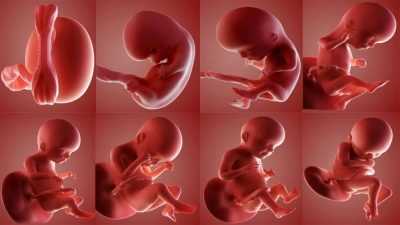

Ультразвуковое исследование для установления срока беременности и ПДР наиболее эффективно только на ранних сроках — до 10-12 недель беременности. Потом появляется большая погрешность. Дело в том, что эмбрионы растут приблизительно с одинаковой скоростью, и пока идут процессы эмбриогенеза, развитие всех малышей протекает почти одинаково.

Потом, когда все органы и системы сформированы, начинается период фетальный, в ходе которого плод растёт и набирает вес. И делать это он уже будет по своей личной генетической программе, которую унаследовал от родителей: одни дети высокие, другие — низкие; одни имеют больший вес, другие — меньший, а потому дети одинакового гестационного возраста могут отличаться параметрами фетометрии.

Пол ребёнка также имеет значение — мальчики обычно растут в утробе чуть быстрее девочек. И срок беременности установить становится сложно.

Важно лишь знать, что наиболее точно установить срок при ультразвуковом обследовании можно лишь на ранних сроках. Это связано с тем, что все эмбрионы в период эмбриогенеза (до 9-10 недели по акушерскому сроку) растут примерно с одинаковой скоростью.

Потом в силу вступают генетические факторы, индивидуальная программа развития: одному малышу, родители которого не отличаются высоким ростом, суждено быть некрупным и небольшим в росте, а другой уже с середины беременности будет иметь внушительные ростовые и весовые показатели.